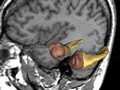

• Segmentation of the hippocampus using a multi-scale shape based method.

We represent and learn the shape in a multi-scale method and then perform the segmentation of the hippocampus.

• The method is tested, using the leave-one-out scheme, on the MR images (SPGR).